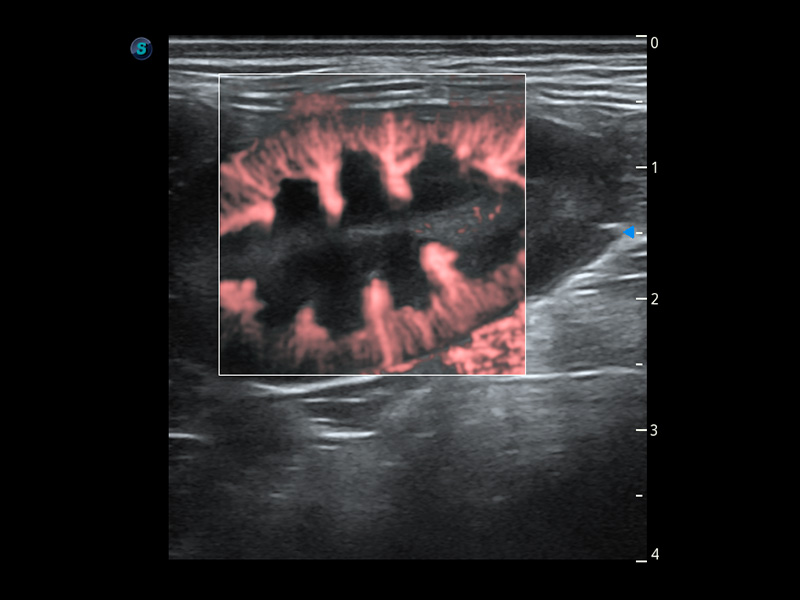

ProPet 60 作为一款高端台式动物超声设备,为动物医生的日常诊断提供了一系列贴合动物临床需求、解决临床实际问题的高级成像功能。凭借全系列高清探头,满足医生对腹部、心脏、生殖、浅表、肌骨等成像的所有需求,切实帮助您提升检查效率,提高诊断信心。

动物是人类最亲密的朋友和最值得信赖的伙伴。哈哈体育官网也一直致力于探索动物专用的超声影像解决方案。 全新推出的ProPet系列,是哈哈体育官网在动物超声影像智能化、专业化、精准化的一次跨越式革新。动物不能用言语来表述自己的不适,通过超声影像,ProPet系列搭建了动物医生与不同物种沟通的“桥梁”,为动物医生注入了“治愈之力”。